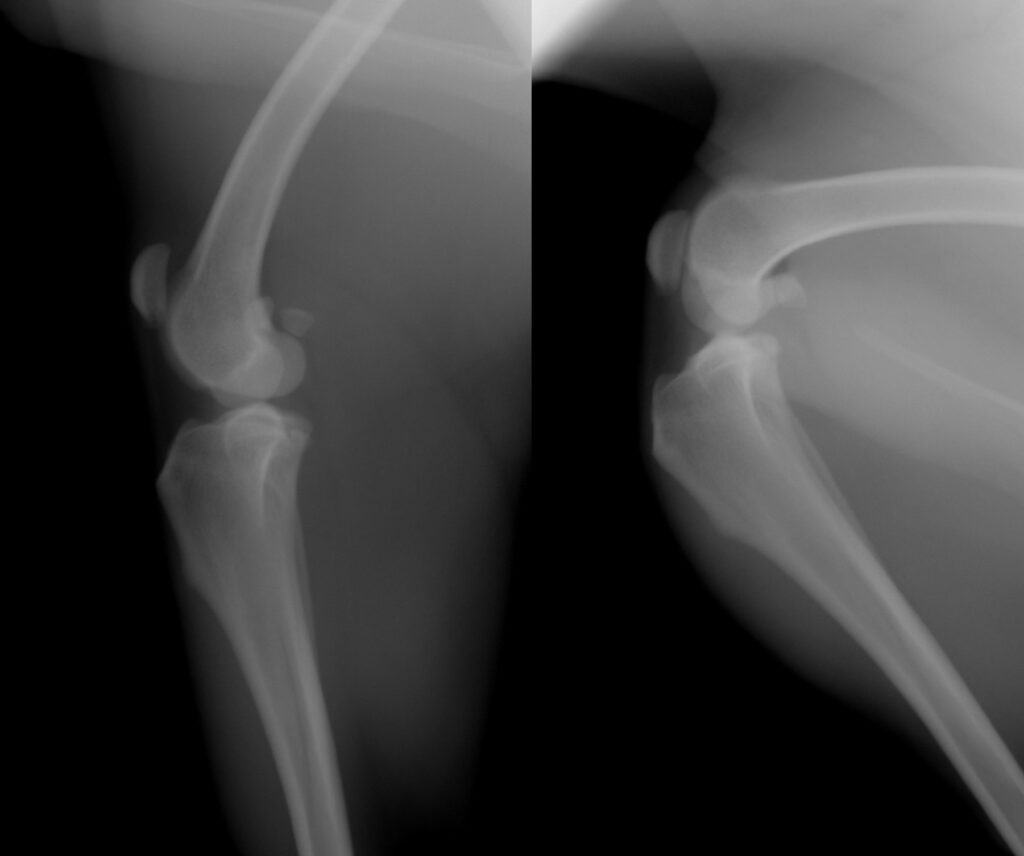

では、実際にはどうでしょうか。下のレントゲン写真は、同じ膝関節を、伸ばした状態と曲げた状態で観察したものです。

曲げ伸ばしで起こる関節の変化に図形を当てはめてみましょう。

上図のように。実際の膝関節は、円と円の構造というよりは、楕円と円の構造になっています。楕円の長軸と単軸の半径の違いによって、曲げ伸ばしの際の中心点間の距離が変わります。このため、前述した、『膝を曲げた状態に合わせて人工繊維を設置すると膝を伸ばした時には緩くなり、膝を伸ばした状態に合わせて設置すれば膝を曲げた時に人工繊維に過剰な力がかかってしまう』という問題が発生してしまい、これがECRの欠点となってしまっていました。